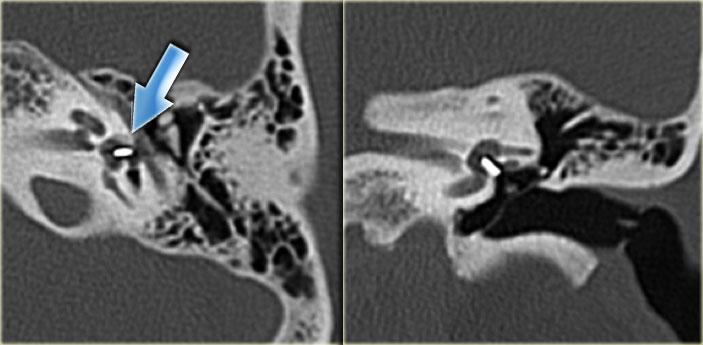

Bên trái là hình ảnh của một bé trai 10 tuổi, được lên kế hoạch cấy ốc tai điện tử.

Có sự giãn rộng và ngắn lại của ống bán khuyên ngoài.

Tiền đình tương đối lớn (mũi tên).

Bên trái là hình ảnh của một bé trai 16 tuổi, được khám tiền phẫu vì cholesteatoma tai phải.

Là một phát hiện tình cờ, có hình ảnh ống bán khuyên ngoài phình to (mũi tên vàng) và vắng mặt ống bán khuyên trên (mũi tên xanh dương).

Tại vị trí dự kiến của ống bán khuyên trên chỉ quan sát thấy một gờ nhỏ.

Ống bán khuyên sau bình thường.